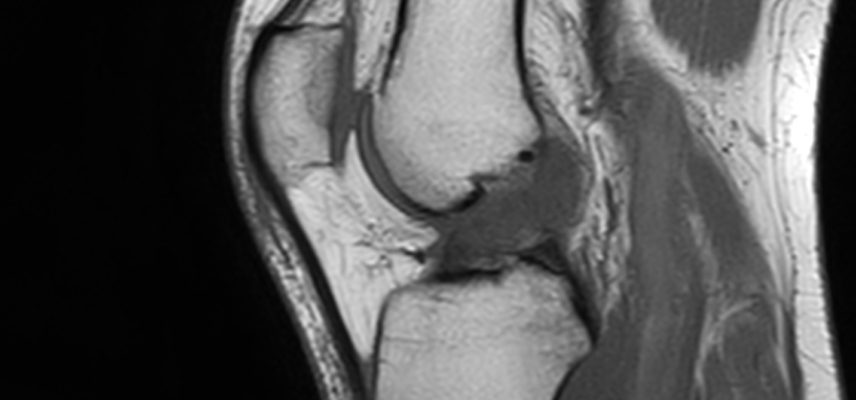

Zerwanie więzadła krzyżowego przedniego to uszkodzenie, które prowadzi do niestabilności stawu kolanowego. W wielu przypadkach, zwłaszcza u osób aktywnych fizycznie i sportowców, rekonstrukcja chirurgiczna jest zalecana. Operacja polega na zastąpieniu uszkodzonego więzadła nowym przeszczepem (np. z własnych ścięgien pacjenta najczęściej z mięśnia półścięgnistego i smukłego). Celem jest przywrócenie stabilności kolana, co jest niezbędne do bezpiecznego powrotu do sportu i codziennego funkcjonowania.